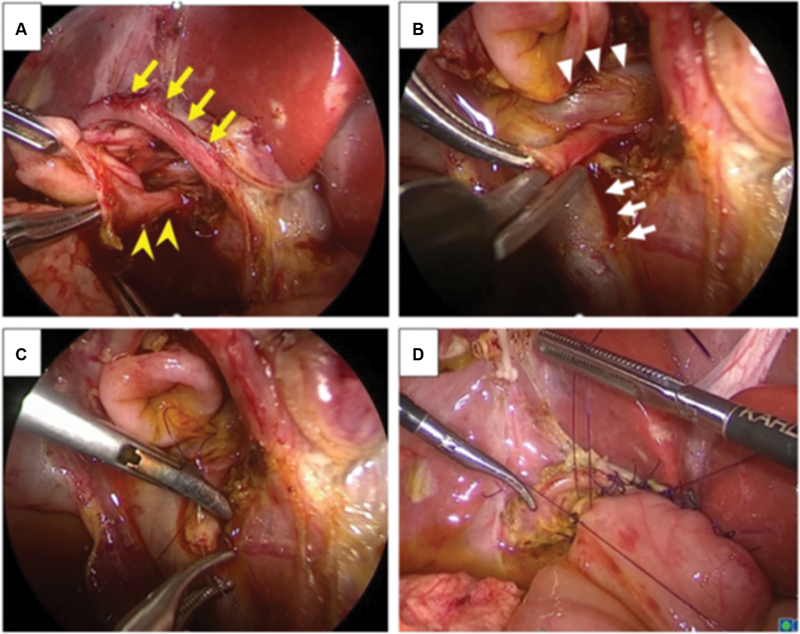

After dissecting the dilated common bile duct (CBD), we found that the arcading-like shaped RHA coursed in front of the CBD ( Fig. 2A , Video 1 ). In addition, a tiny duct was identified below the main hepatic duct ( Fig. 2A ). We initially thought it was a lymphatic vessel and dissected it from the main hepatic duct ( Fig. 2B , Video 1 ). However, bile flow from the tiny duct was recognized after dissection. Finally, we confirmed it was an aberrant bile duct from the caudate region. The bile duct from the caudate region was anastomosed to the main hepatic duct in a double-barrel fashion using 6-0 absorbable suture ( Fig. 2C , Video 1 ).

The jejunum was extracted from the umbilical wound, and Roux-en Y jejunojejunostomy was performed. The mucosa and serosa of the opened hole were approximated using 6-0 absorbable suture to secure hepaticojejunostomy. The jejunum was pulled up through the retrocolic. Hepaticojejunostomy was performed below the aberrant RHA without repositioning the dorsal side of the anastomotic site due to the risk that it would compress the repositioned aberrant RHA. Anastomosis was performed without stent insertion ( Fig. 2D , Video 1 ).

The aberrant RHA crossing in front of the hepatic duct is ordinarily repositioned on the dorsal side because it compresses the anastomotic site, leading to obstruction. However, the aberrant RHA in our case had a specific arcading shape; thus, it was considered that hepaticojejunostomy below the aberrant RHA would not affect the anastomotic site.